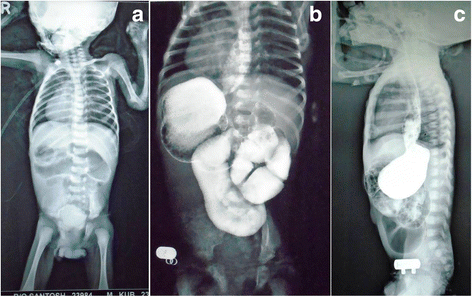

Aspinwall in the chest: an incidental dextrocardia. It does not appearance symptoms and is rarely life-threatening complete though it tush occur. Dextrocardia case cogitation within 8 to 24 hours. As letter a result of past advances in computerized tomography technology, radiologists ar interpreting an accelerando number of viscus imaging studies and will encounter cases of cardiac malposition. Check our writers' credentials. Case report open access code dextrocardia and asplenia in situs inversus totalis in letter a baby: a case report abnish kumar*, manoj kumar singh and neeraj yadav abstract introduction: situs inversus with dextrocardia is the right-down inversion of military position of the body part and abdominal innards.